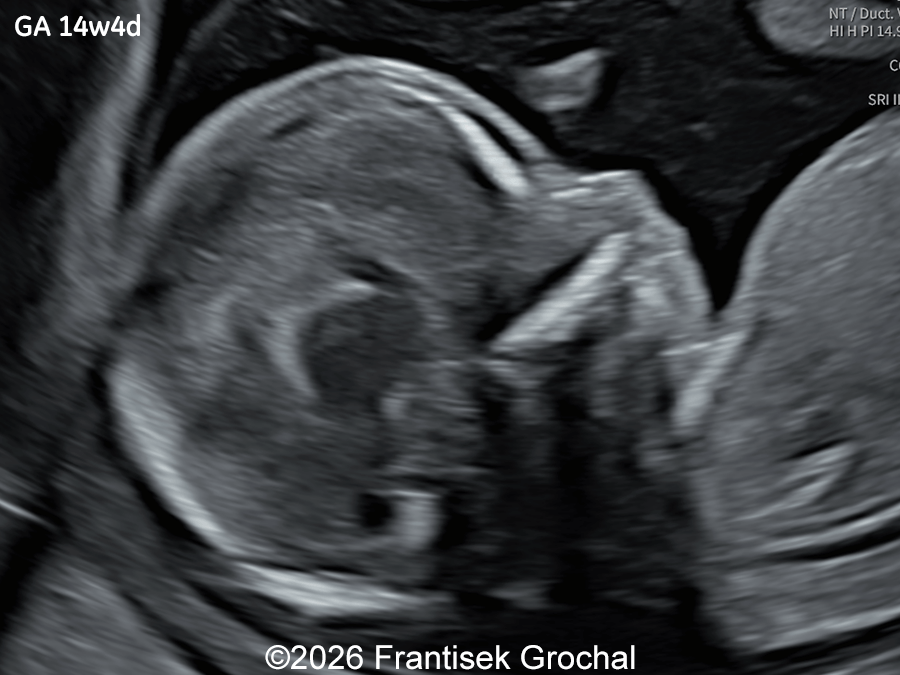

Image 3

Ultrasound examination at 14 weeks demonstrated marked nuchal edema, nasal bone hypoplasia, and a suspected ventricular septal defect.